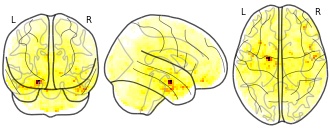

Affect Label: Amyg Connectivity, Label - Blur: RPV

License information was derived automaticallyArea coveredRancho Palos VerdesDescriptionspm_spm: resels per voxel

Collection description

Neurodevelopmental Changes Across Adolescence in Viewing and Labeling Dynamic Peer Emotions

Adolescence is a sensitive period of social-affective development, characterized by biological, neurological, and social changes. The field currently conceptualizes these changes in terms of an imbalance between systems supporting reactivity and regulation, specifically nonlinear changes in reactivity networks and linear changes in regulatory networks. Previous research suggests that the labeling or reappraisal of emotion increases activity in lateral prefrontal cortex (LPFC), and decreases activity in amygdala relative to passive viewing of affective stimuli. However, past work in this area has relied heavily on paradigms using static, adult faces, as well as explicit regulation. In the current study, we assessed cross-sectional trends in neural responses to viewing and labeling dynamic peer emotional expressions in adolescent girls 10-23 years old. Our dynamic adolescent stimuli set reliably and robustly recruited key brain regions involved in emotion reactivity (MOFC/vMPFC, bilateral amygdala) and regulation (bilateral dorsal and ventral LPFC). However, contrary to the age-trends predicted by the dominant models in studies of risk/reward, the LPFC showed a nonlinear age trend across adolescence to labeling dynamic peer faces, whereas the MOFC/vMPFC showed a linear decrease with age to viewing dynamic peer faces. There were no significant age trends observed in the amygdala.Subject species

homo sapiens

Map type

Other